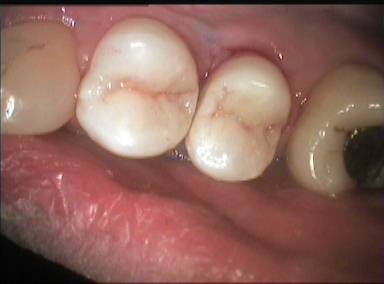

et les compos terminés quand même, premier cas avec les loupes.

004 urylgv - Eugenol

Images 1 qtgoxf - Eugenol